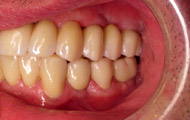

Exemple de 3 dents manquantes remplacées par 3 couronnes sur implants.

Pose des piliers prothétiques et des 3 couronnes scellées.